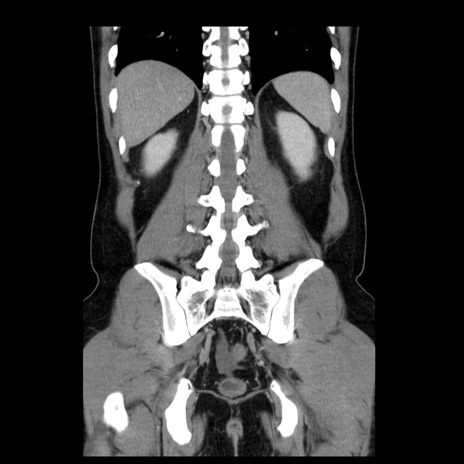

症例4(冠状断像)

横断像